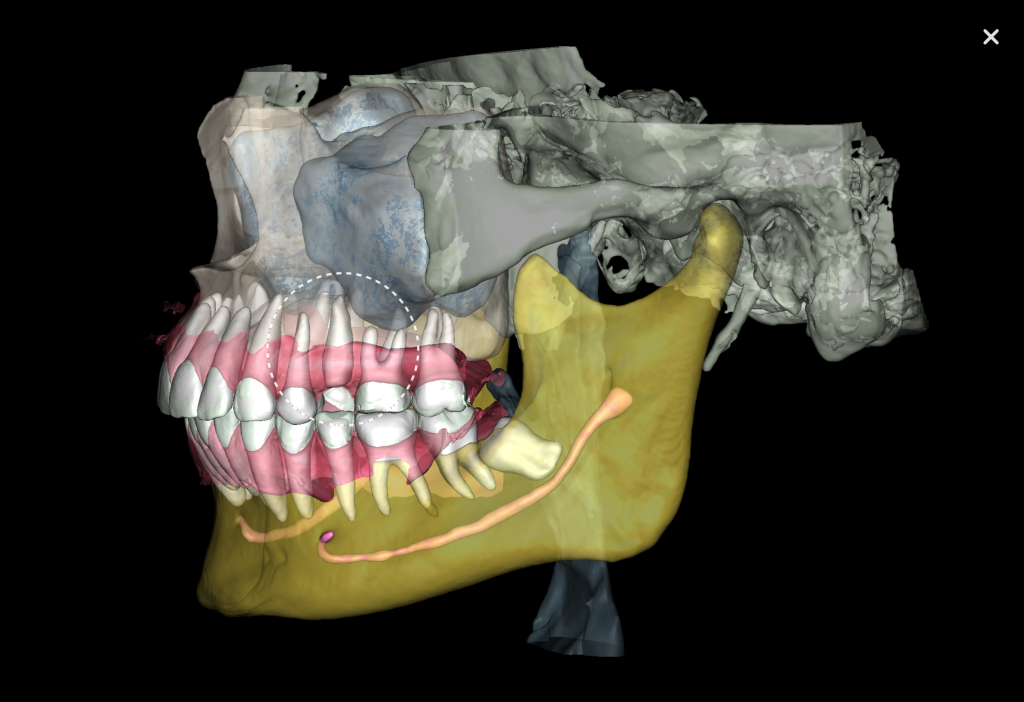

Virtual models of the template for guided implant surgery can be created using the “STL” module of Diagnocat. To do this, intraoral scan data is loaded into the module, and a suitable CBCT is selected for merging

Collaborating with Diagnocat AI in treatment planning can increase the quality and accuracy of the procedure, ensuring the long-term success of dental implant surgery